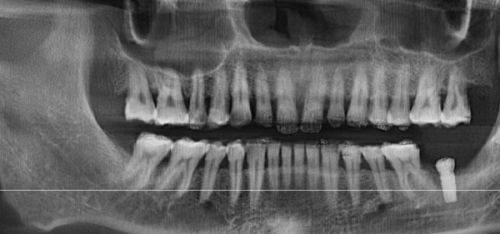

种牙是一项对技术和经验要求特别高的口腔治疗项目,特别多患者都担心种牙的成效和安心性。那么,北京劲松口腔(方庄店)种牙靠谱吗?我们可以从医生和患者口碑两个方面来了解。

从医生方面来看,前面我们已经介绍了北京劲松口腔(方庄店)的医生团队,他们不仅专精技术实力强,而且临床经验多。在种牙过程中,医生会进行详细的口腔检查和评估,制定科学合理的种植方案,确保种牙的成功几率和成效。

从患者口碑方面来看,特别多在该医院种牙的患者都给出了高度评价。有患者表示,从挂号到种牙,整个过程都非常顺利,医院的服务周到细致,医生的技术也非常好,种完牙后没有出现任何不适,而且牙齿的功能和美观度都达到了预期成效。